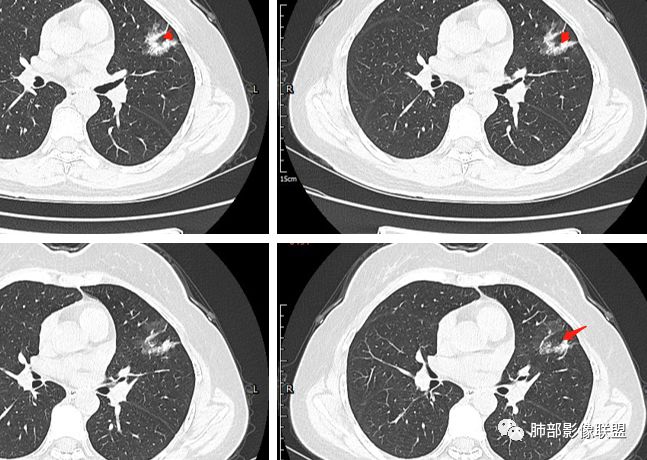

左肺上叶胸膜下不规则结节影,分叶、粗短毛刺,胸膜牵拉等,像个“刺头”。

未见钙化,也未显示液化坏死或空洞。

与支气管相关,但取层未能显示支气管进入情况。

有几点应当引起我们高度重视:

1.病灶周围向几个方向膨出的边界清楚的磨玻璃影,这些磨玻璃影时隔几个月依然,几乎可以排除出血及一般的炎性改变。

2.病灶的胸膜牵拉线与其间病灶胸膜侧的磨玻璃边构成朝向胸壁的“月牙铲”结构,这种影像学表现某种程度上反映出病理学特征——病灶收缩+小叶间隔阻挡。

3.病灶实性密度区强化明显,这有助于我们区分一些其他类似病灶,如结核灶等!

4.邻近未见树芽征及卫星灶等。

结合临床,应当高度怀疑浸润性肺腺癌!

二.关于胸膜下小结节:

结节影太小,尚未能够充分反映出影像学特征。随访观察应当是恰当的处置方式。